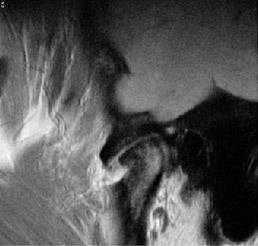

Заднее смещение диска.

Заднее смещение диска (составляет менее 0,01% всех патологий ВНЧС).

А. Положение с закрытым ртом. Суставной диск сместился дорзально.

Б.Положение с открытым ртом. Возвращение суставного диска на уровень мыщелка нижней челюсти. Движения челюсти очень ограничены в данном случае.